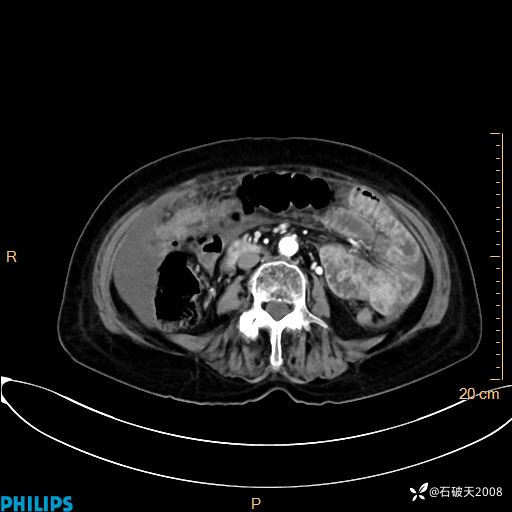

MIP